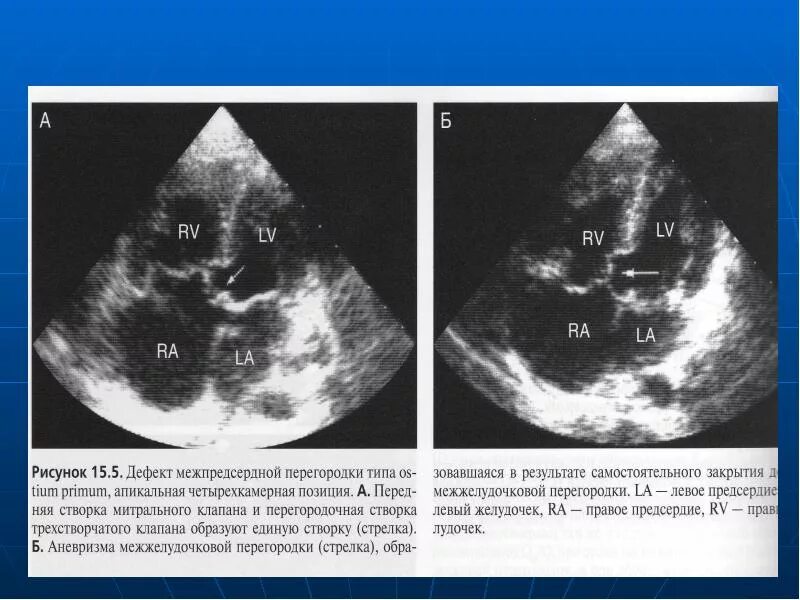

Аневризма мпп без